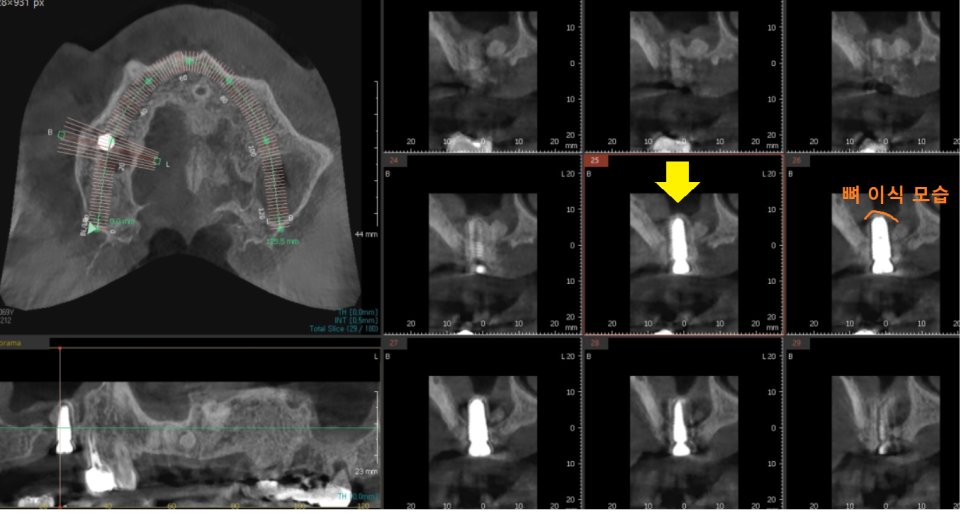

23.12.12

3D CT를 사용하여

모의 수술을 진행

안전하게 수술 완료했습니다.

환자분은 뼈가 많이 없어서

발치 후 뼈이식

뼈가 만들어지고 임플란트와 함께 뼈이식

뼈이식만 2번 진행했는데요.